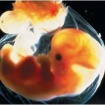

6. týden